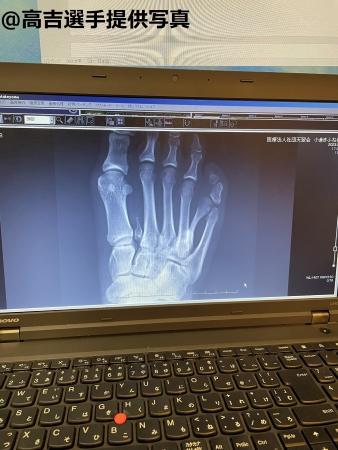

(高吉の足の異常は)先天性多合趾症(センテンセイタゴウシショウ)というんですけど、普通は多指症と言ってきれいに6本指が生えているんですよ。

自分は親指ほどの大きさの指がもう1本(枝分かれするような形で)生えていて、(足の指の)爪が割れて合体していた。

それで(片足に)1本あって、生まれて間もないときに(両足から1本ずつ)切断しました。